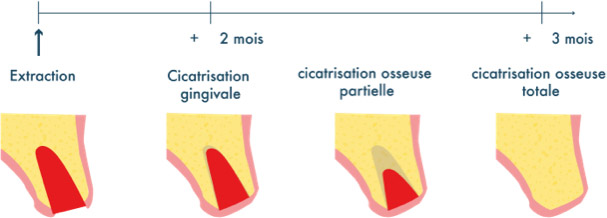

La préservation alvéolaire

Reconstruction de la zone qui favorise la mise en place d’un implant pour remplacer la dent absente (avant & après)